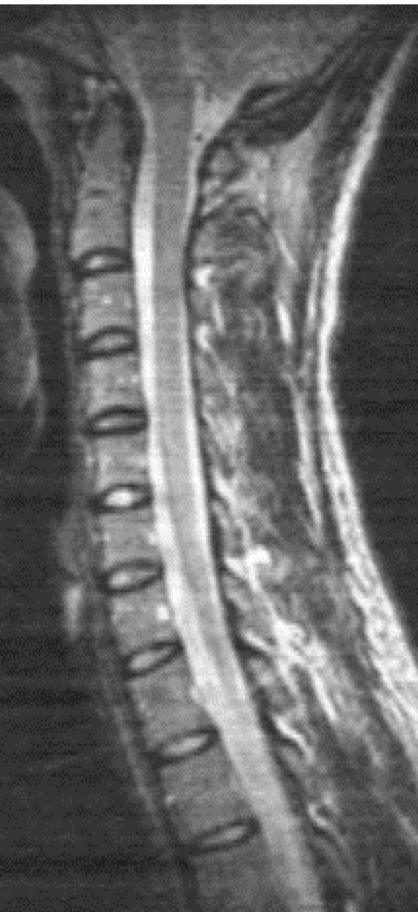

Is this a T1 or T2 weighted MRI? Why?

T2 weighted because fluid filled cavities (CSF, spinal cord and IVDs) are opaque